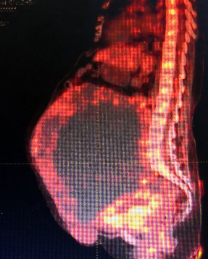

腹部巨大包块影像检查

入院后,团队对王女士进行了详细的身体检查,一方面排除血栓的可能,并予以低分子肝素对症治疗,另一方面考虑到患者左侧胸腔积水,请胸外科进行胸腔穿刺引流,并由介入科对盆腔的巨大包块进行造影检查,明确了包块血供不是来源于大血管,麻醉科、输血科、SICU等科室进行了多学科会诊,充分做好了手术准备。

3月25日,在充分告知相关手术风险后,上海十院妇产科程忠平团队为王女士进行了“盆腔肿瘤切除术+肠粘连松解术+大网膜切除术+子宫颈切除术+双侧卵巢切除术+盆腔淋巴结切除术+腹壁肿瘤切除术”。术中发现盆腔包块来源于左侧卵巢,其血供主要来源于横结肠及肠系膜,包块与肠管和系膜无明显界限,因此在术中又邀请了普外科周波主任共同手术,分开了肿块,保住了肠管。

术中发现患者盆腔包块里的囊液足足有6000ml,实体包块净重3.5kg,病理结果确认是子宫平滑肌肉瘤。经历长达6小时后,手术取得成功,患者安返ICU,在ICU观察一夜后,第二天就转回妇科病房。虽说手术对王女士来说这次手术只是第一步,后续还需要化疗,但是终于可以不再携带着近20斤的包块生活了,八年来重新赢回自由呼吸、自如活动,让她和家人都感激不已。10天后患者康复出院,出院时特意送来了3面锦旗表达感谢。